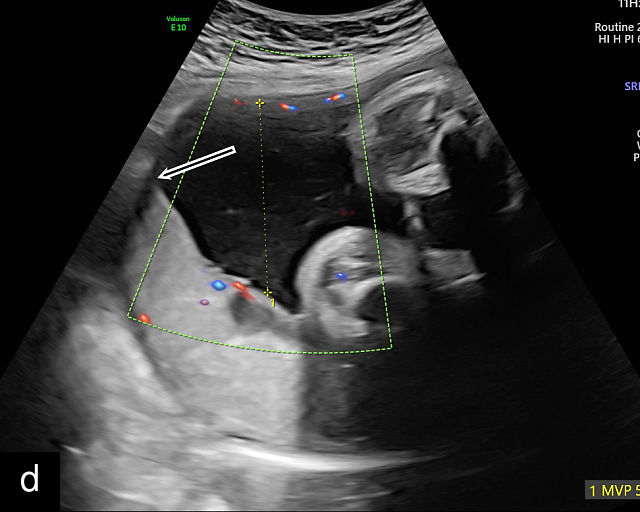

- The umbilical cord insertion (Figure 2b,c) and placental margin (Figure 2d) – Special attention should be paid to the site at which the umbilical cord or vessels insert into the placenta, as well as the marginal regions of the placenta, to identify potential abnormalities.

(a) Transabdominal grayscale ultrasound image of the placenta showing the four key placental regions: the myometrium (gray area), decidua (black line), chorion (light gray thin line), placental body (p), and the chorion–amnion interface. (b) Grayscale ultrasound image of the umbilical cord insertion into the placenta. (c) Same view as in (b) but with color Doppler applied. (d) Normal placental edge (arrow), which is a common location for placental lakes. (e) Rolled placental edges (arrows) in circumvallate placenta (p).